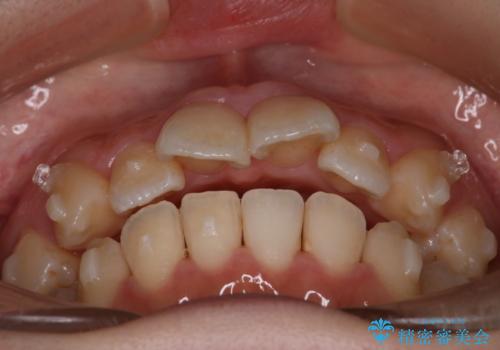

【インビザライン】マウスピースで開咬改善

- 開咬を主訴に来院されました。

IPR(歯と歯の間を削る処置)と顎間ゴムを行いながら、インビザラインで開咬を治療する計画を立てました。

治療をしながら、MFT(口腔筋機能療法)も行っていくことにしました。

歯の移動量が多いケースでしたが、患者様にマウスピースの使用とゴム掛けを頑張っていただいたので

リファイメント1回のみで治療を終わることができました。